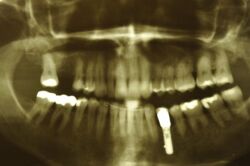

Patientin aus Fulda zur Präparation der Unterkieferseitenzähne für Laborgefertigte Dauerprovisorien

Große Probleme wegen vorhandener Wurzelreosprtionen, vermutlich in Folge einer kieferorthopädischen Behandlung in den 90er Jahren

Dann stellt sich heraus, dass die bisherige Vermutung im Übersichtsröntgenbild (OPG) seien die Wurtzeln der Seitenzähne außerhalb der Schicht nicht sichtbar, dass an den Backenzähnen erhebliche Wurzelresorptionen stattgefunden haben, vermutlich das Ergebnis einer in den 90er Jahren durchgeführten Erwachsenenkieferorthopädie.

Faktenlage ist: Sie sind da, es besteht die Notwendigkeit, nach umfangreicher Karies unter einer riesengroßen Kunststofffüllung unter Zahn 36 den Nerv zu eröffnen und nunmehr mit den vorliegenden Wurzelresorptionen einen suffiziente Wurzelkanalbehandlung durchzuführen.